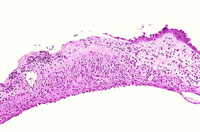

Visit the NTP WebsiteChronic inflammation of the gallbladder with mucosal ulceration.